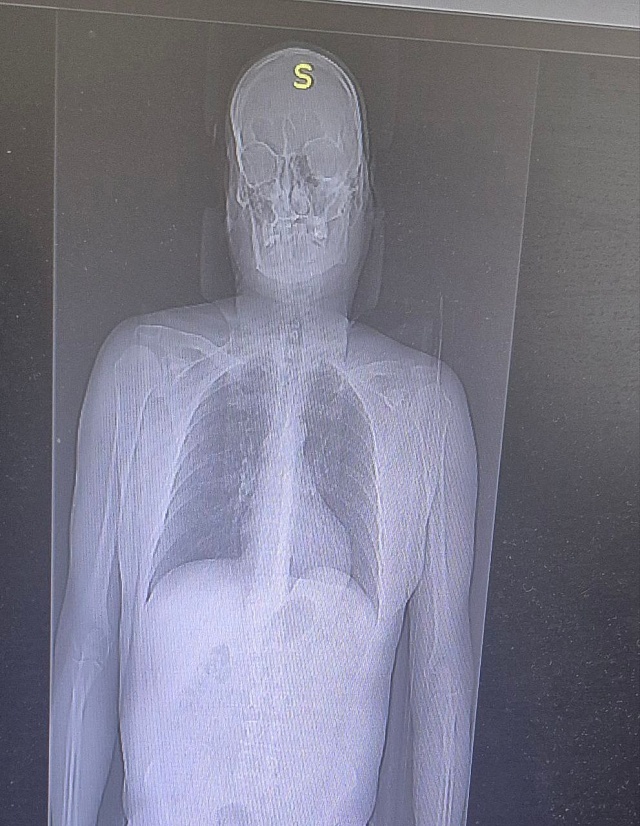

По результатам обследований у мужчины диагностировали переломы двух ребер и ушибы мягких тканей. Благодаря быстрой диагностике, грамотному обезболиванию и профессиональной помощи состояние пациента стабилизировали. Уже на следующей неделе он будет готовиться к выписке.